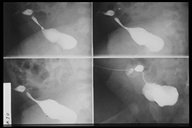

A catheter is introduce through the fistula for fistulogram

Plain X-ray showed that the catheter is located in the suprapubic region which is most likely in the bladder

Contrast study fills the bladder proving the fistula to be a patent urachus

Fistulogram demonstrates the tract connecting the umbilicus and the urinary bladder